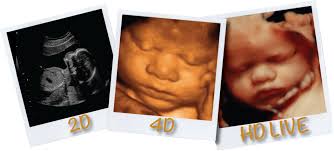

四维彩超的基础还是二维,是一种超声波对腹部扫描,形成的图像用软件处理,就成了我们看到的立体图像,对胎儿是没有伤害的。